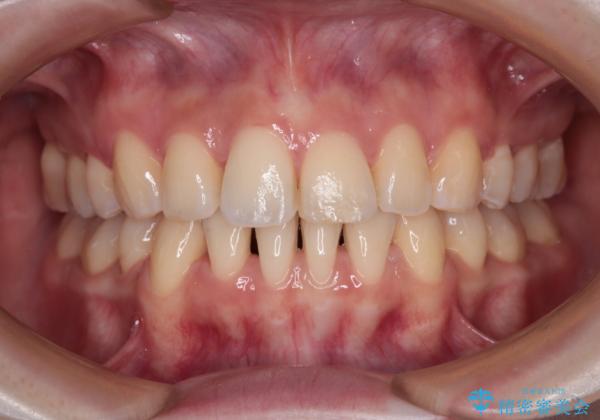

【モニター】飛び出した上顎前歯を抜歯矯正で引っ込める ワイヤー装置の抜歯矯正治療

- 口元の閉じにくさを気にして来院された患者様です。

上下ともに歯列が前方に突出していたため、上下左右の第一小臼歯4本を抜去し、ワイヤー装置による矯正治療を行うこととしました。

舌の突出癖による影響もあったため、舌のトレーニングを並行して実施しました。

舌の突出癖がなかなか改善されず、上下前歯の接触がやや甘い状態での仕上がりとなりました。

接触が甘い場合、上顎前歯の叢生が後戻りを起こしやすくなるため、治療終了後の保定期間でも舌のトレーニングを継続するように指示しています。